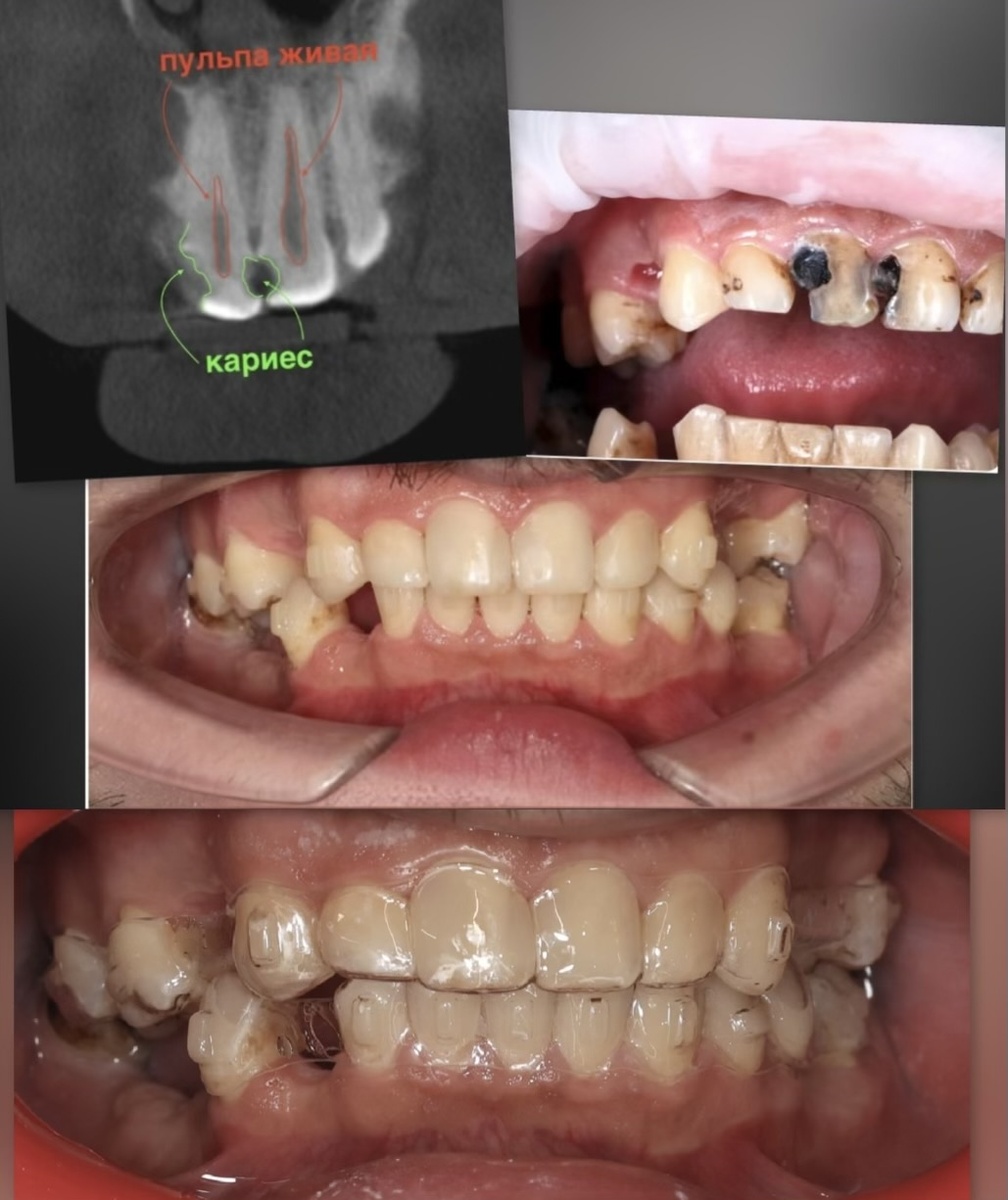

Это продолжение истории нашего пациента, которого вы уже знаете по некоторым предыдущим материалам. В сентябре 2023 года мы начали спасать его зубы - кариес на грани пульпита, несколько зубов под вопросом, что-то удаляли. Потом, в феврале 2025, установили элайнеры. И вот, в декабре 2025, новый этап - установка сразу четырех имплантатов на нижнюю челюсть. От ортодонта отмашка получена, действуем. Но обо всём по порядку. Что имеем за такой срок? Большая часть успеха в сложных случаях - это сам пациент. Врачи могут составить идеальный план, но если человек не приходит на приёмы и не выполняет рекомендации - дела плохи. Когда лечение затрагивает несколько специальностей (терапию, хирургию, ортопедию, ортодонтию) - кто-то один должен координировать процесс. В случаях с исправлением прикуса это ортодонт. Почему? Потому что положение зубов меняется. Нельзя поставить имплантат в октябре, если в декабре зубы сдвинутся и места станет больше или меньше. Нельзя делать постоянные коронки, пока при

Это продолжение истории нашего пациента, которого вы уже знаете по некоторым предыдущим материалам. В сентябре 2023 года мы начали спасать его зубы - кариес на грани пульпита, несколько зубов под вопросом, что-то удаляли. Потом, в феврале 2025, установили элайнеры.

Коллаж

И вот, в декабре 2025, новый этап - установка сразу четырех имплантатов на нижнюю челюсть. От ортодонта отмашка получена, действуем.